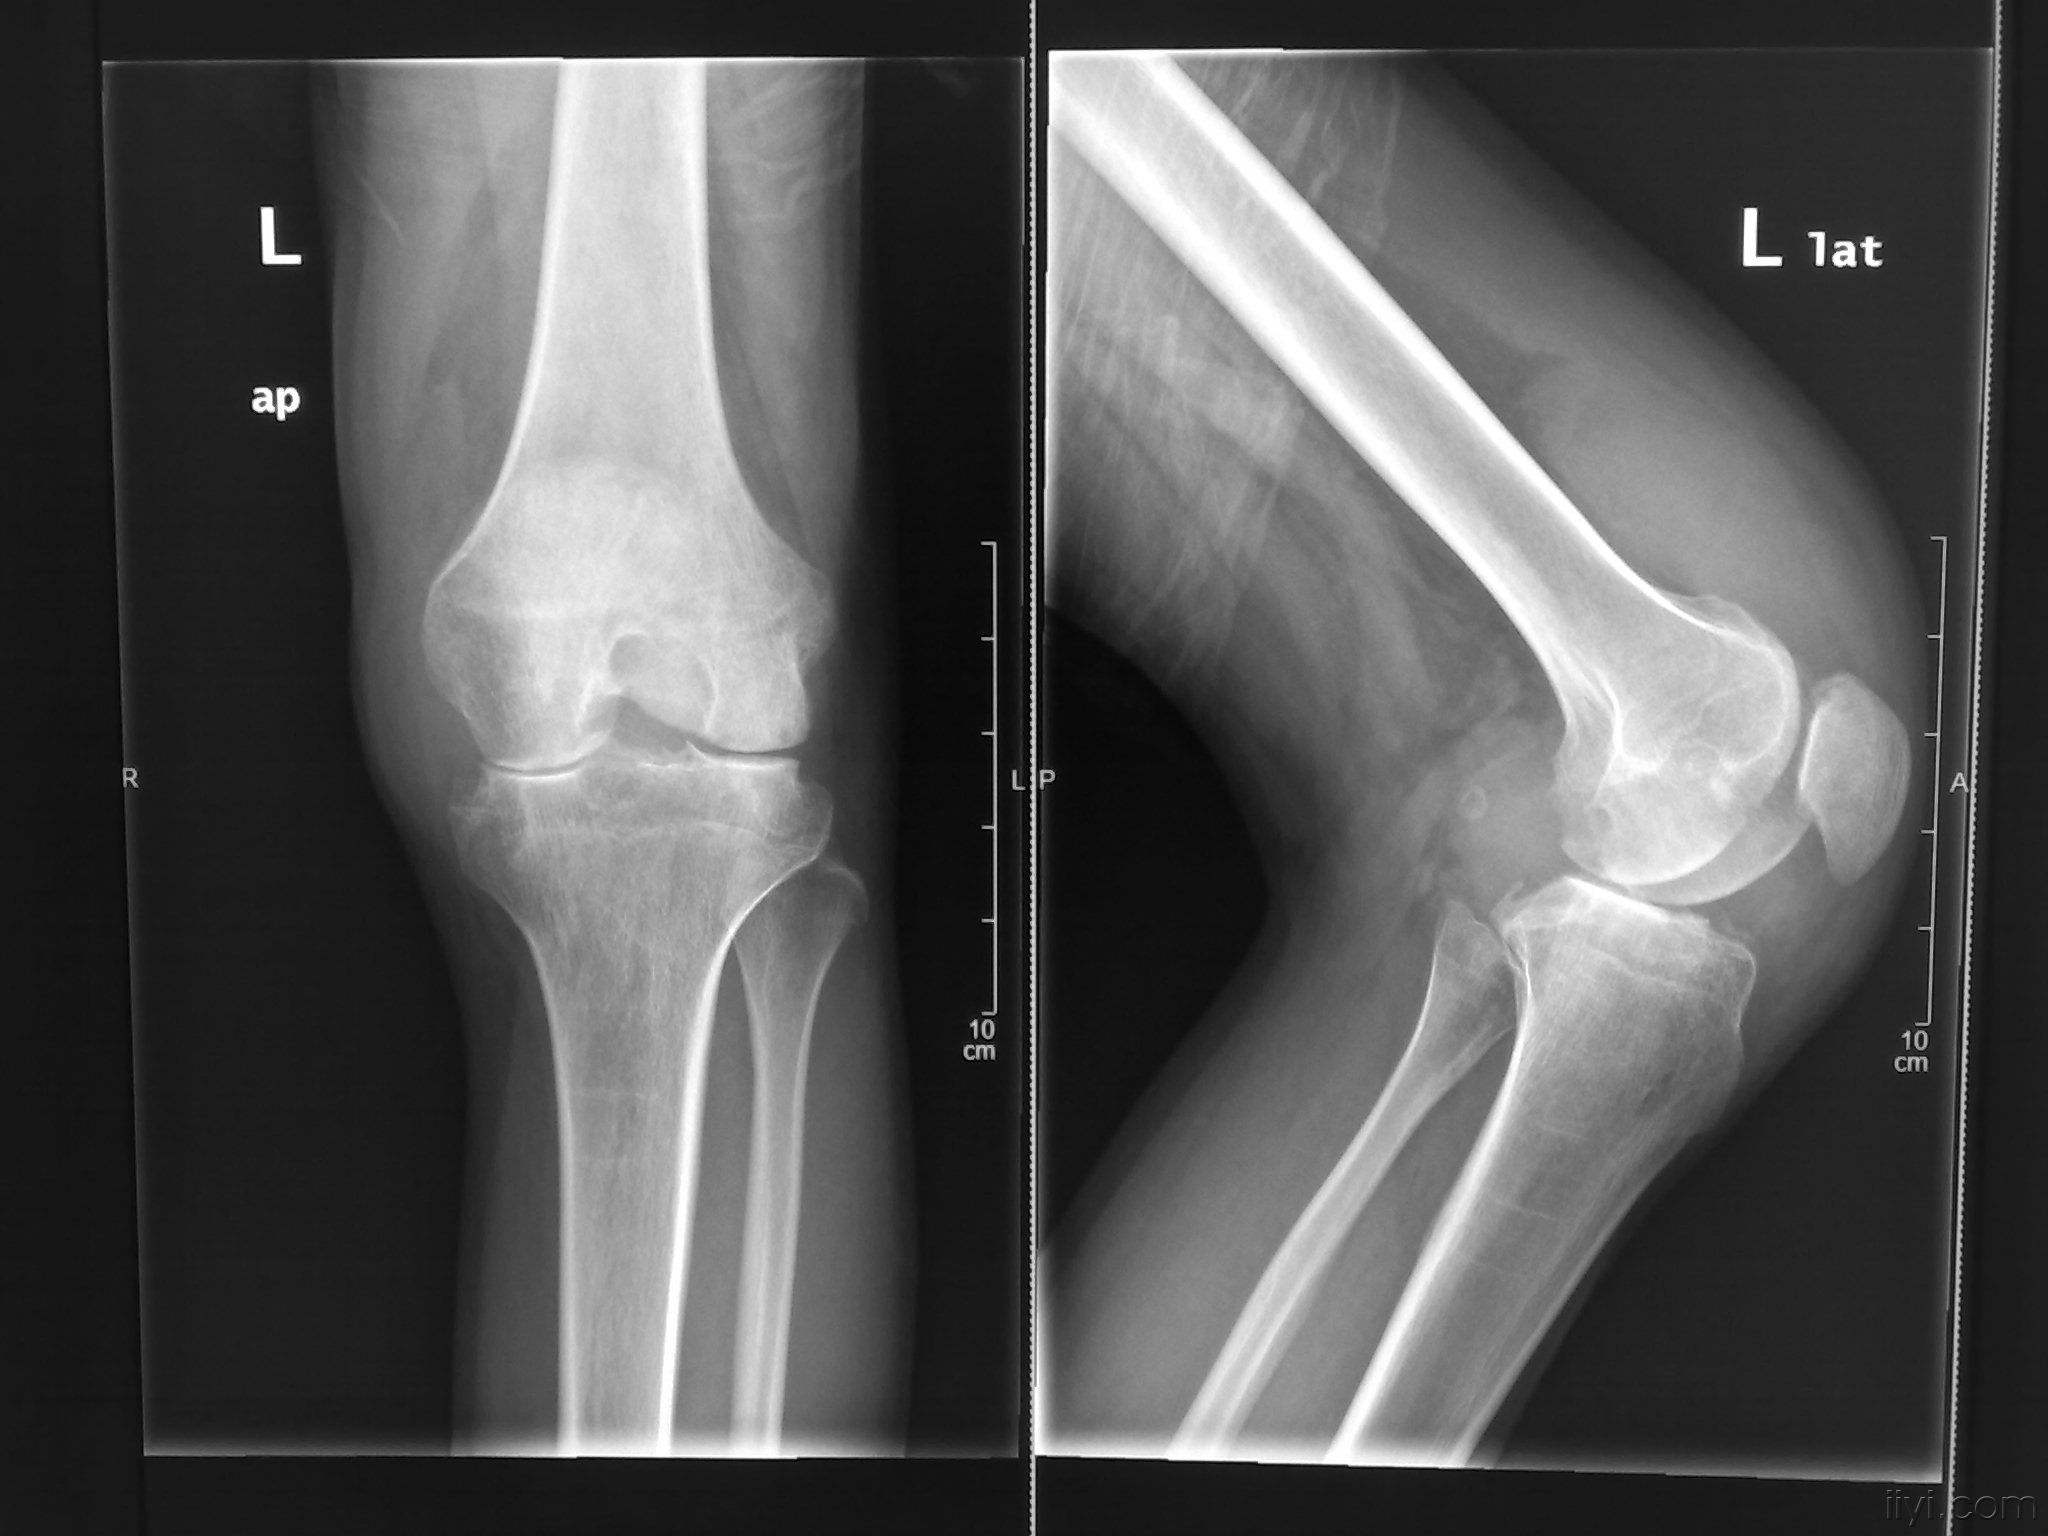

类风湿是一种发病慢,但是可以累及到骨骼以及周围组织的一种 ...

类风湿是一种很常见的病症,在临床上主要表现为以关节症状为 ...

类风湿是一种自身免疫性疾病,它具有炎症性、进行性、破坏性 ...